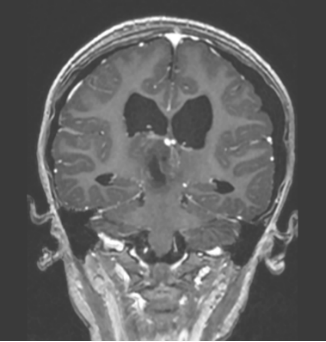

患儿术后MRI图像

术后病理考虑为颅内间叶源性肿瘤,非脑膜上皮来源。FISH提示EWSR1不典型断裂阳性。术后MRI显示肿瘤完全切除。目前患儿情况稳定,由ICU转入普通病房。

患儿术后MR影像:松果体区肿瘤组织切除完全